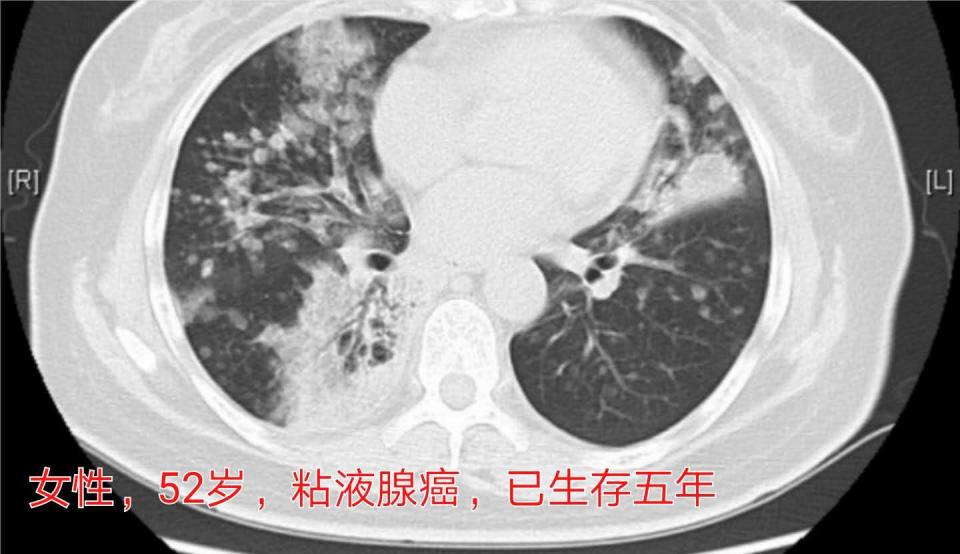

4.女性52岁,双肺粘液性腺癌(合并了气道播散),做过6次化疗和2种靶向药物治疗,生存五年多:

这是首都北京的一位病人,当初在军总医院进修学习时候遇到的,最后一次复查,控制得还不错:

遗憾的是进修结束之后就没有继续跟踪,不知道老人还在不在。